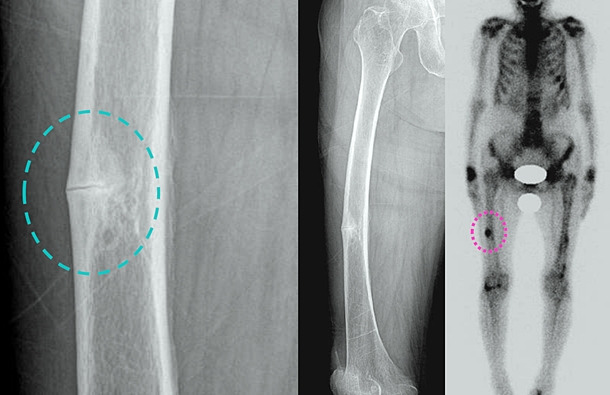

정답은 바로 골다공증입니다. 조용히 진행되다가, 넘어지는 순간 존재감을 드러내는 무서운 병이죠.

- 뼈가 서서히 약해짐: 겉보기엔 멀쩡해 보여도 속은 텅텅.

- 첫 신호가 ‘골절’: 손목·척추·고관절 골절로 뒤늦게 발견되는 경우가 많아요.